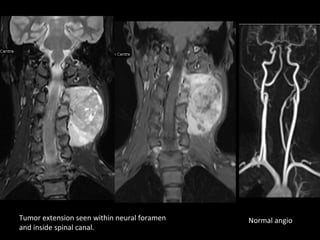

Large left posterior triangle mass with

neuroforaminal extension.

Tumor extension seen within neural foramen   Normal angio

and inside spinal canal.

Diagnosis -Neurogenic tumor

• MRI is ideal in assessing intraspinal /